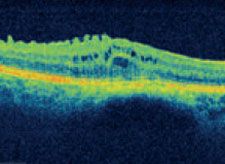

Die optische Koherenztomographie in spectral Technik (auch bekannt als „Spectralis“, Fourier Domain OCT oder 3D – OCT) ist die modernste und genauste Methode zur Darstellung von Netzhautveränderungen.

Mithilfe modernster Algorithmen und Analyseverfahren kann das Cirrus HD-OCT einzigartig detaillierte HD-Darstellungen erzeugen.

Altersbedingte Makuladegeneration

- HD-OCT-Bilder sind hochauflösende Querschnitte, welche die Pathologie bis ins kleinste Detail darstellen.

- Das HD-OCT-Bild zeigt die Netzhautschichten bis ins kleinste Detail. Die genaue Position dieses Bildes ist auf dem LSO-Fundusbild angegeben.